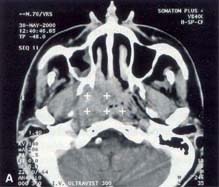

Εικόνα

2. Καρκίνος του ρινοφάρυγγα πριν (Α) και μετά (Β) τη θεραπεία με

ακτινοβολία.